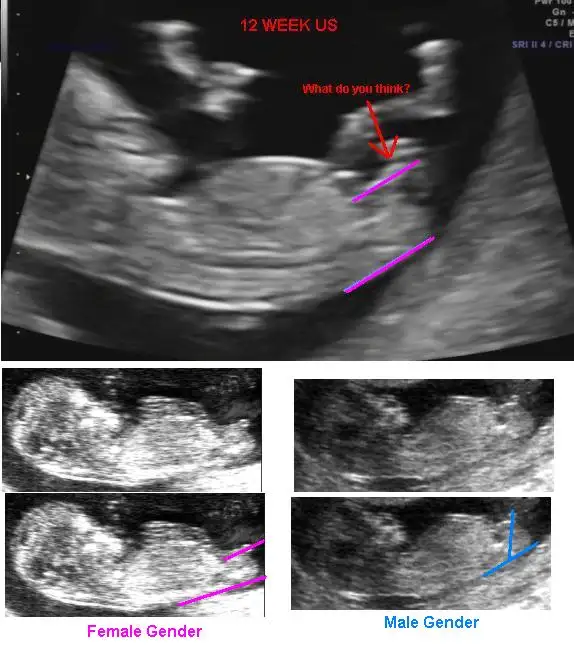

Bebeğinizin cinsiyeti ne olacak ?

• $BoyOrGirl2.webp

$BoyOrGirl2.webp

29,3 KB · Görüntüleme: 80